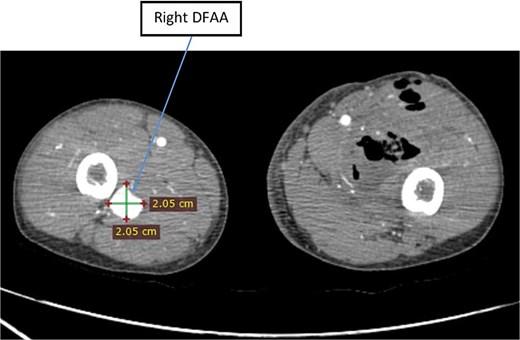

White blood cell count was 13,700 and hemoglobin was 3.4 mg/dl. CTA revealed bilateral DFAAs with the left measuring a maximal diameter of 9.32 mm with adjacent surgical pack pushing the vessels medially and a right concentric unruptured DFAA measuring 2.05 cm (Figs 1–3).

Axial image of lower limb CTA showing right unruptured DFAA with concentric aneurysmal sac.